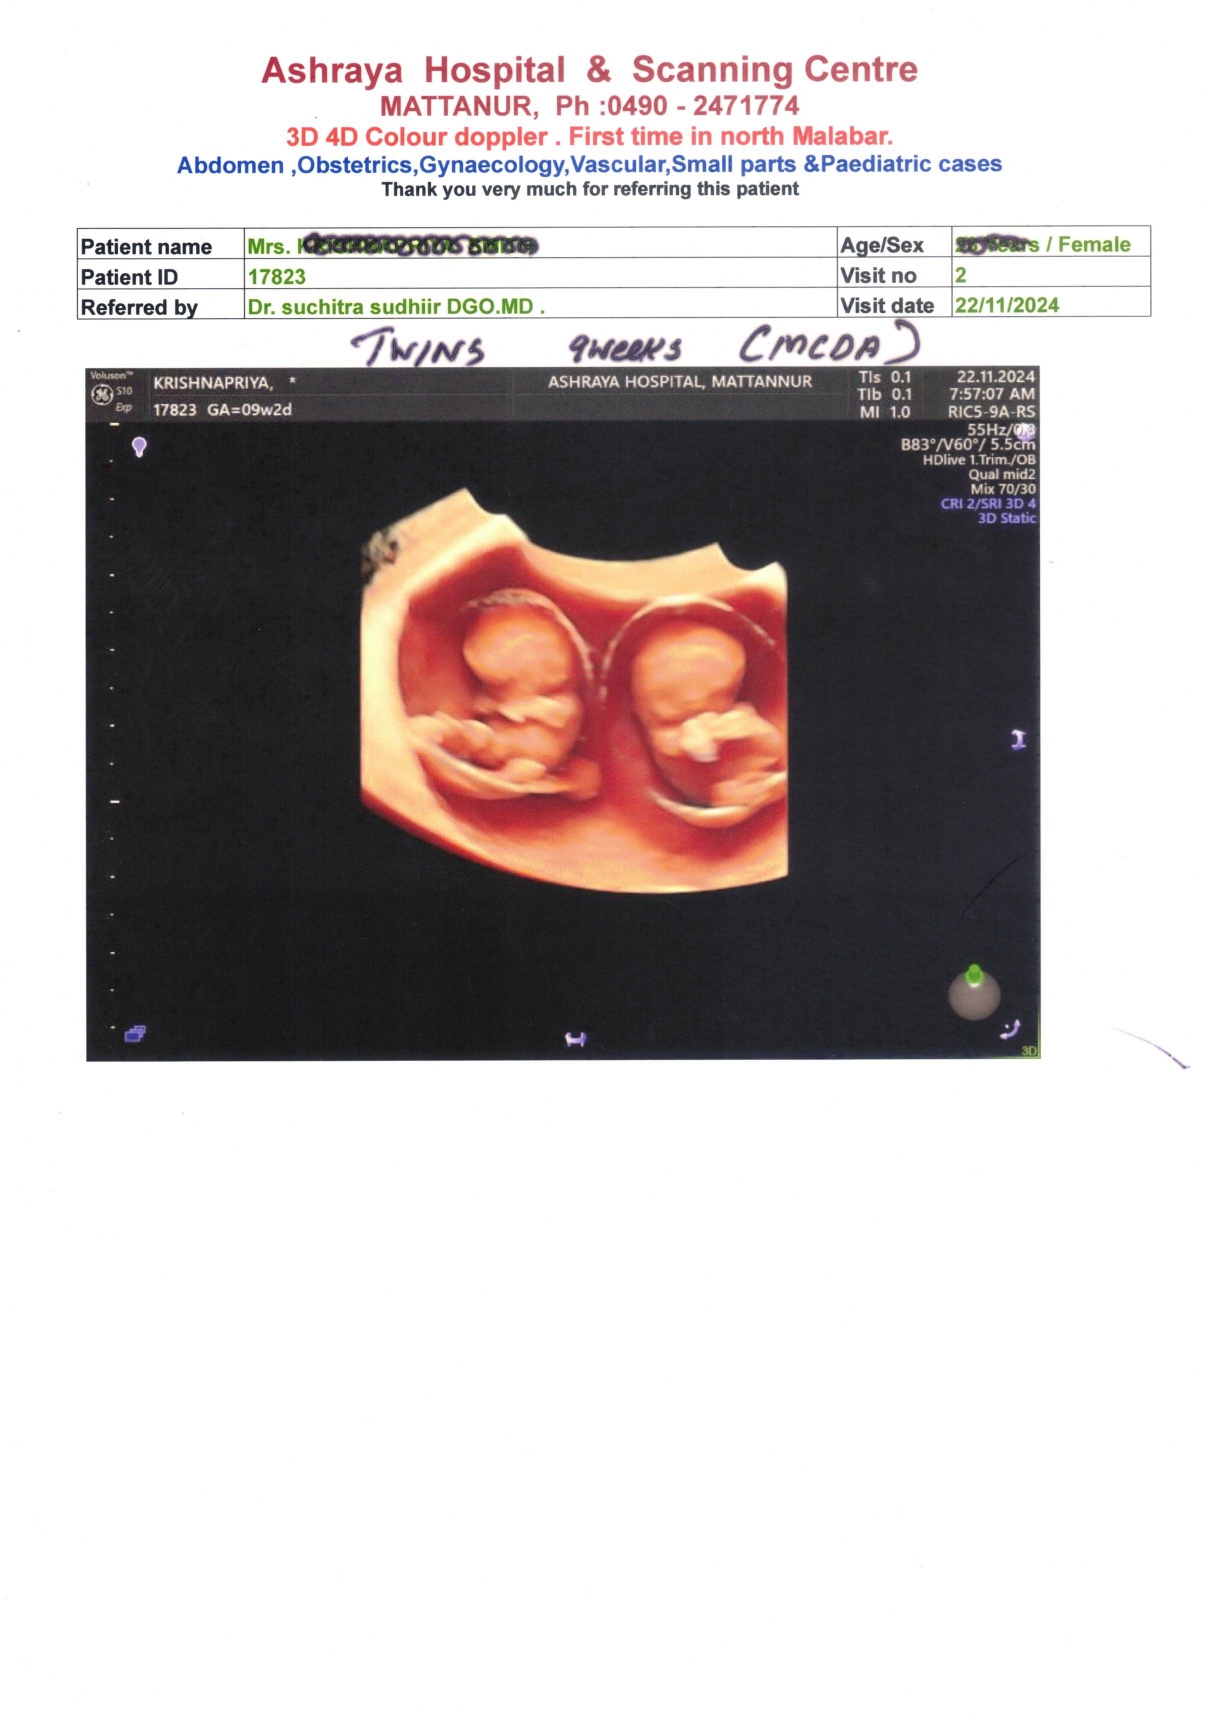

SCANNING REPORT OF 9 WEEKS FETAL